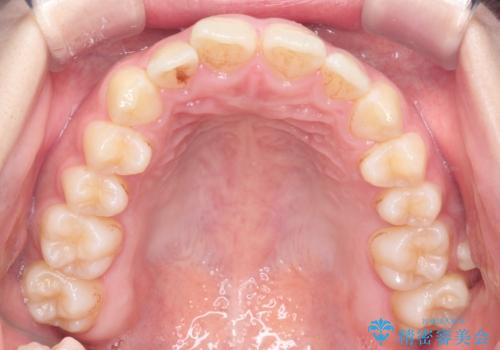

- 患者様は、**下の前歯のがたつき(叢生)**を気にされて来院されました。

できるだけ目立たずに治療を進めたいというご希望があったため、インビザラインによるマウスピース矯正をご提案しました。

診査の結果、インビザラインでの対応が可能と判断し、全体の咬合バランスにも配慮した上で、治療計画を立てました。

下の前歯のがたつきは解消され、滑らかなアーチ状の歯並びとなりました。

目立たずに治療が進んだことに対しても、患者様から高い満足のお声をいただきました。